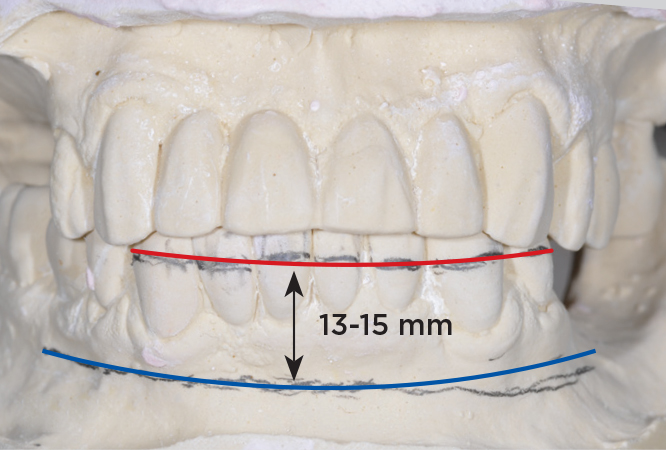

An important advantage of this approach is the ability to simulate bone reduction on the models and verify the presence of 15 mm to 17 mm and 13 mm to 15 mm of required inter-occlusal space for maxillary and mandibular restorations, respectively. This creates a platform for a diagnostic wax-up of the proposed dental rehabilitation and fabrication of wax prosthesis try-ins when necessary. Finally, a modified All-on-4 provisional prosthesis surgical and restorative guide developed by the authors for restoration-driven surgery and simplified restorative procedures is fabricated (Figure 2 through Figure 8).

Fig 5. Bone reduction model surgery performed in mandibular arch to create 13 mm to 15 mm of inter-occlusal space required for the mandibular All-on-4 provisional restoration.

Figure 5